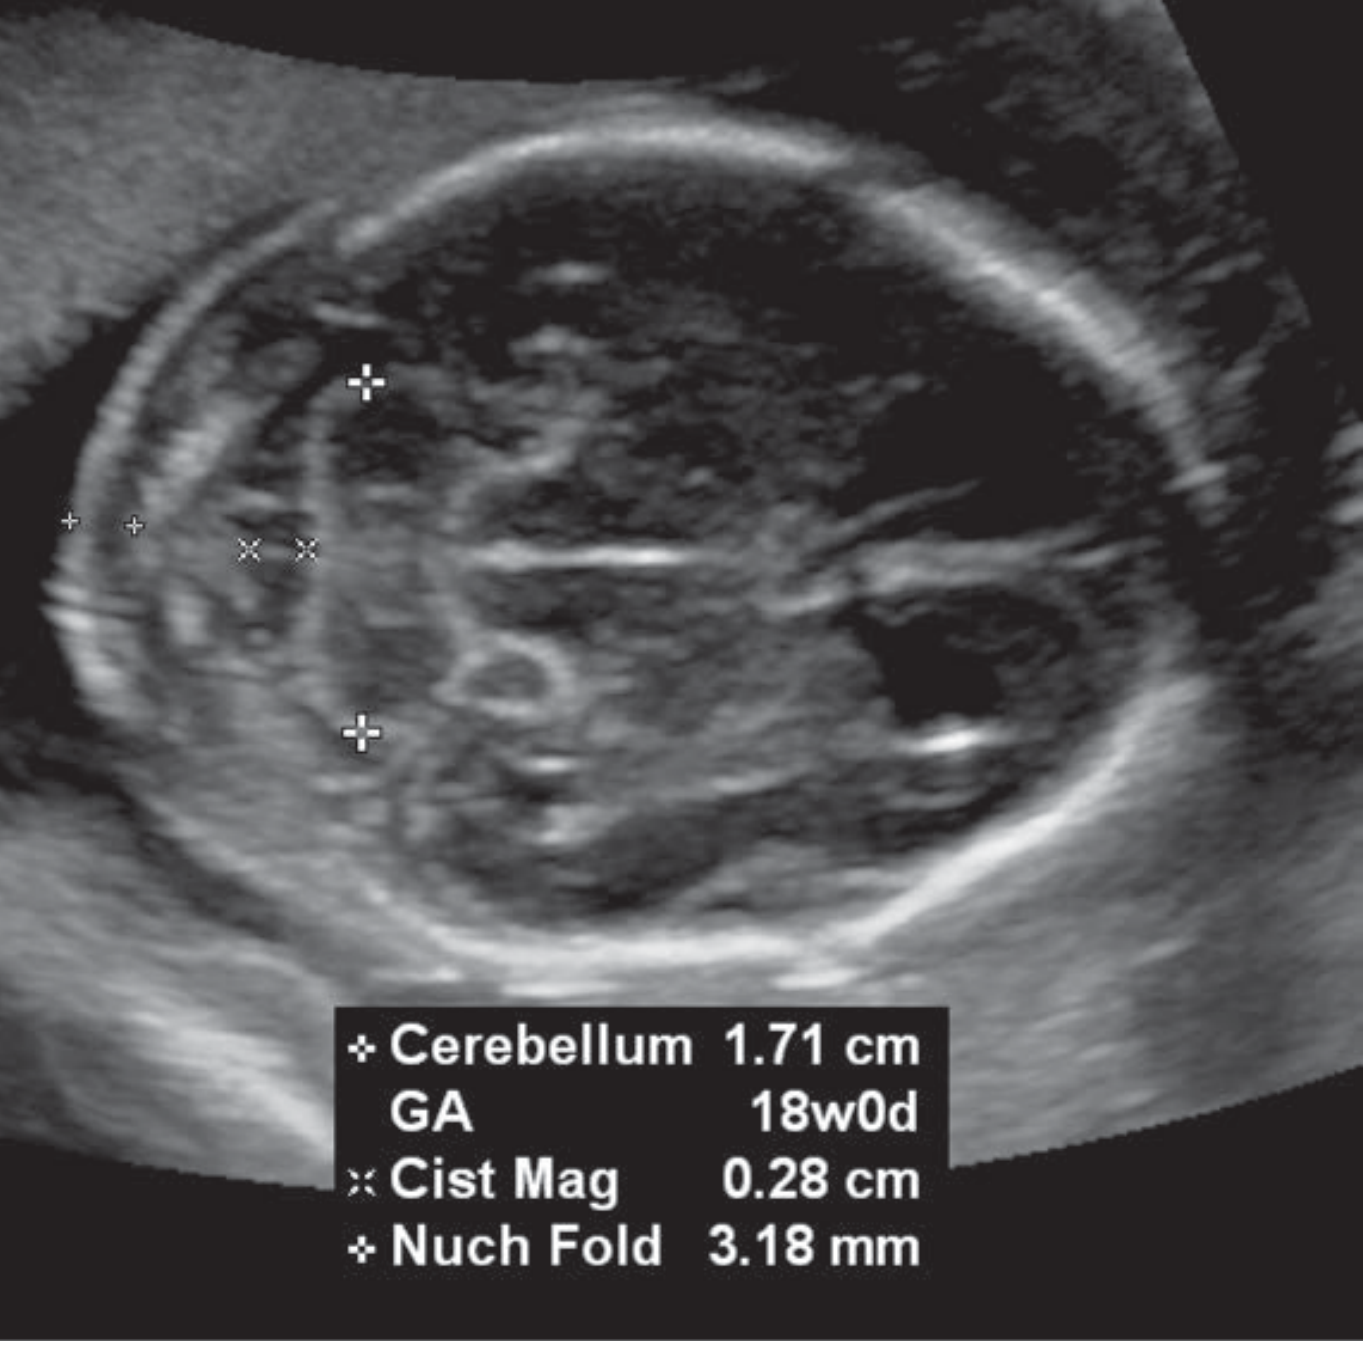

Posterior fossa — cerebellum and nuchal fold

Figure: Posterior fossa — cerebellum and nuchal fold measurement

Nuchal fold ≥ 6 mmTrisomy 21